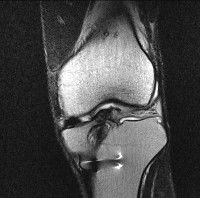

무릎 mri 간단히 봐주실 수 있으시나요 ㅠㅠ

안녕하세요 8년전 십자인대 수술하고 최근 무리한 운동에 무릎 불편감이 생겨서

mri 찍었습니다.

진단결과는 첫 찍은 병원에서 활액막염 이라는 진단을 받았습니다. 혹시 봐주실 수 있으실까요?

올라온 MRI가 단편적이라서 정확한 진단에 어려움이 있지만 십자인대에는 큰 이상이 있지는 않은것 같으며, 무릎관절내 물이 있는 것으로 보아 활액막염의 진단이 맞을 것 같습니다.

하지만 단편적인 영상이기 때문에 촬영병원에서 정확한 판독지 등을 받으시는 것이 좋겠습니다.